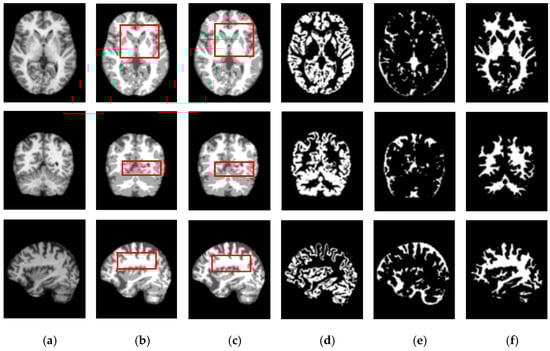

Figure 5 and Figure 6 show the segmentation results for the axial, coronal, and sagittal planes of the OASIS and IBSR datasets, respectively. The figures show that the proposed approach achieves well-segmented performances for GM, WM, and CSF of the brain MRI on both datasets. The axial plane shows the most informative details in the central slices of the MRI compared to the other planes. Thus, the segmentation results for the axial planes show the segmentation performance most effectively. In addition, the highlighted boxes in Figure 5 and Figure 6 show that the quality of sagittal and coronal images is highly promising without any difference in every detail. From the results of Figure 5 and Figure 6, it can be inferred that the proposed method can extract complicated pattern features from all three planes.

Figure 5.

Segmentation results for the axial, coronal, and sagittal planes of the brain MRI image (top to bottom) on the OASIS dataset using the proposed method. (a) Original input images, (b) ground truth segmentation map, (c) their predicted segmentation map obtained by using the proposed method, (d) predicted GM (binary map), (e) predicted CSF (binary map), (f) predicted WM (binary map).